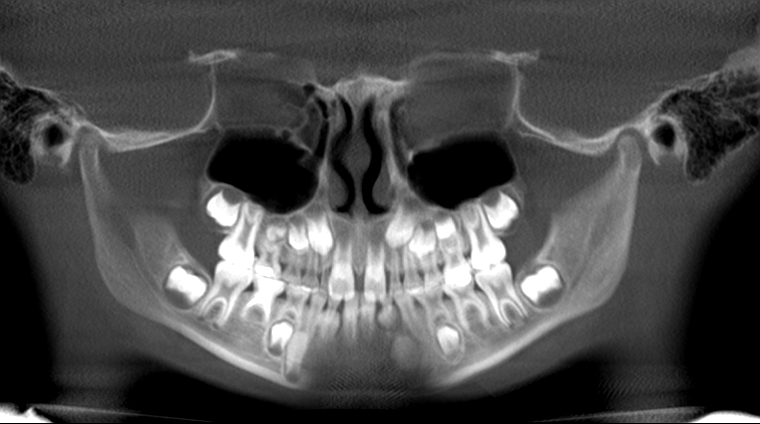

The Hidden Secrets the Panoramic Holds

Missing upper 2's, missing lower 5's, ectopic canines. © 2018 Dr Chris Baker The Panoramic radiograph.  You may be surprised to discover the amazing information you can find about a child patient in that x-ray.  Can you name five really important findings in a panoramic on an early mixed...  Read More

The Problems of missing and ectopic second bicuspids Severely ectopic LR5 had to be removed. © 2018 2 Facts for your consideration:             The “5’s”, or second bicuspids are statistically the third most-commonly congenitally anomalous teeth, misshapen, ectopic eruptive positions, and...  Read More